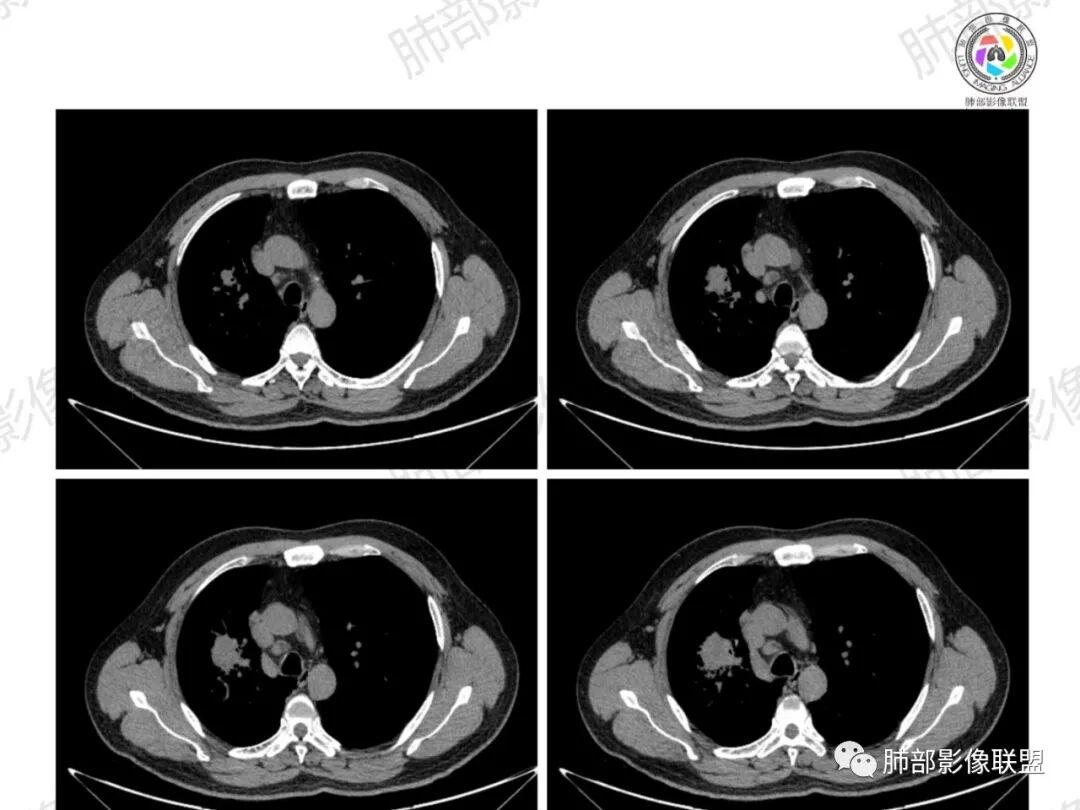

纵隔淋巴结肿大并不明显,就这一个肿大较明显,但仍呈椭圆形,中心少许坏死。

1、坏死区内寸草不生;2、病灶环形强化;3、远端树芽和结节;4、远端不是阻塞性炎症,而是树芽和结节,右肺上叶前后段都有,后段为主,而堵塞的支气管应该是前段;这些树芽的位置不是堵塞支气管的责任区;5、支气管不是突然截断堵塞,而是逐渐狭窄;6、纵隔淋巴结是椭圆形增大,内有坏死,不是肿瘤的圆形饱满;7、支气管周围粘液样坏死,符合仙人掌结核改变;

1、支气管堵塞:这个病例的支气管不是突然截断,而是逐渐狭窄的;

2、湖泊样坏死:这个病例其实不是湖泊样坏死。湖泊样坏死边界不清,周围有水草样改变;这个病例的坏死更像水库,不是湖泊,坏死区边界清楚,里面寸草不生;

4、纵隔淋巴结肿大:这个病例的淋巴结肿大,不是圆形饱满,而是椭圆形,中间坏死。

水库:是人工的,边缘是石头彻的大坝(环形强化类似大坝),坝缘没草长,边界清楚。

湖泊:是天然的,周围没有环形强化的大坝,是逐渐过渡到强化区的,边缘可有细小血管或者坏死不彻底的肿瘤区。